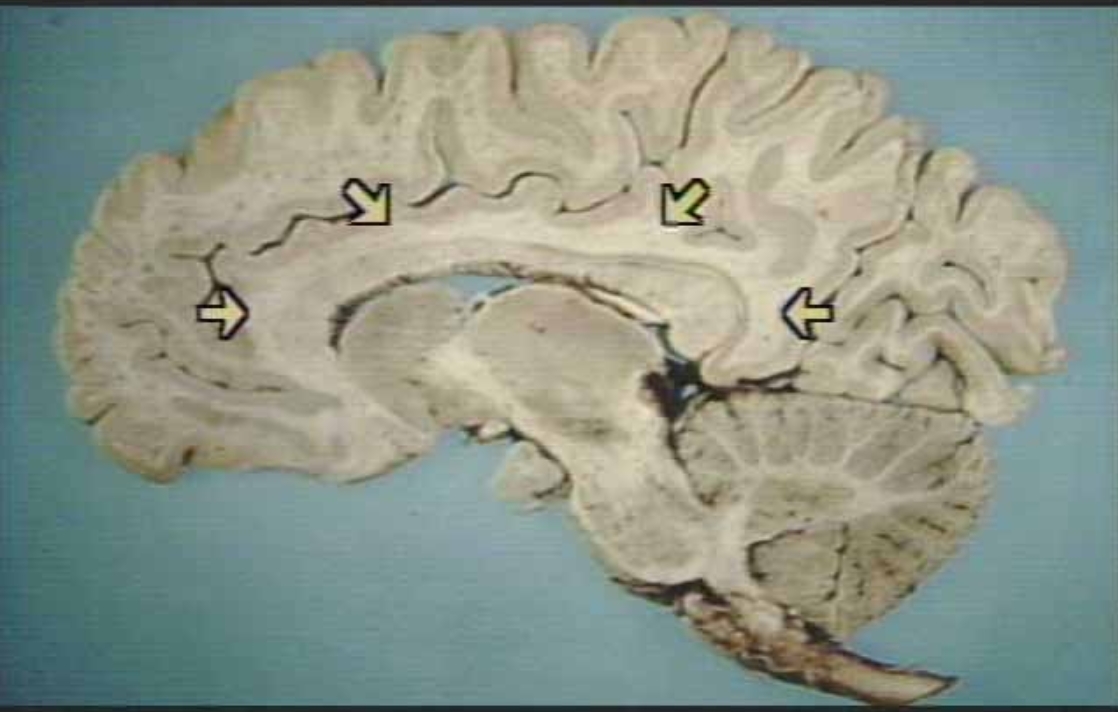

What are the arrows pointing at?

Limbic Region in the cingulate gyrus